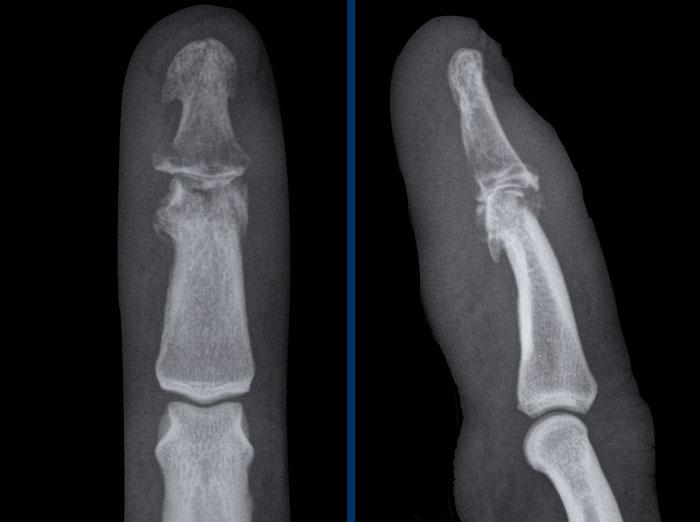

Viêm khớp nhiễm khuẩn tại khớp liên đốt gần (PIP) ngón 3.

Có phù nề mô mềm rất lớn tại ngón 3.

Có các bào mòn lan rộng tại khớp kèm theo một số mảnh xương nhỏ.

Viêm khớp nhiễm trùng là biến chứng của áp-xe đầu ngón tay.

Các dấu hiệu bao gồm:

- Phù nề mô mềm

- Bào mòn và hẹp khe khớp liên đốt xa (DIP).

- Xơ cứng dưới sụn và hình thành gai xương là do thoái hóa khớp thứ phát.